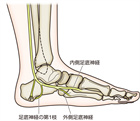

1. 足底腱膜炎は、炎症ではなく過負荷が原因で起こる足底腱膜の微小断裂である。

1. 保存療法では負荷を軽減するためのアキレス腱のストレッチ(推奨度1)と装具療法(推奨度2)を行う。

1. 保存療法無効例には積極的保存療法として体外衝撃波療法(推奨度2)を、手術的治療として鏡視下足底腱膜切離術(推奨度2)や腓腹筋内側頭切離術(推奨度2)を行う。